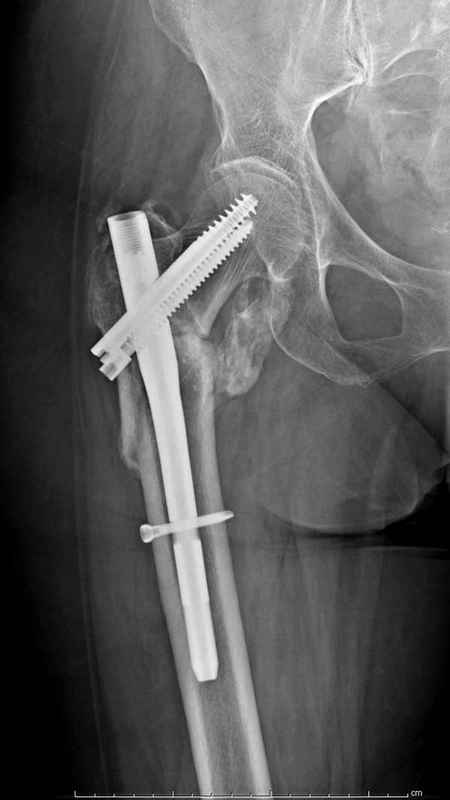

Здесь пара случаев фиксации похожих переломов:

первый высокоэнергетическая травма 36 лет

Здесь 83 года, травма в результате падения